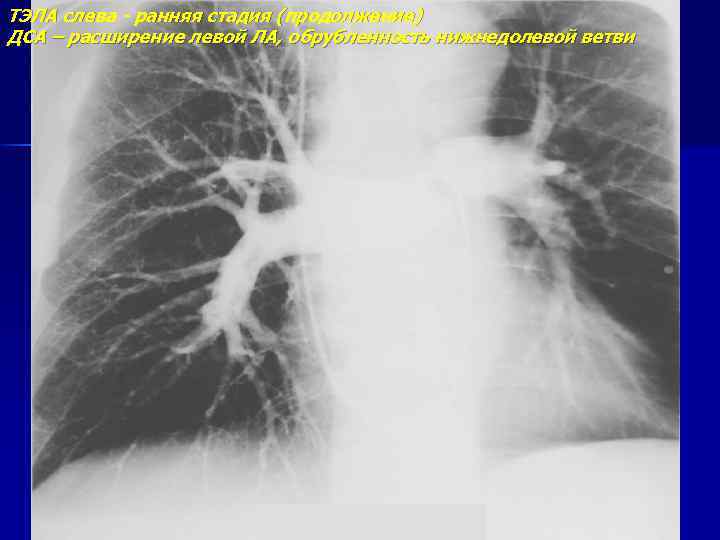

ТЭЛА слева - ранняя стадия (продолжение) ДСА – расширение левой ЛА, обрубленность нижнедолевой ветви